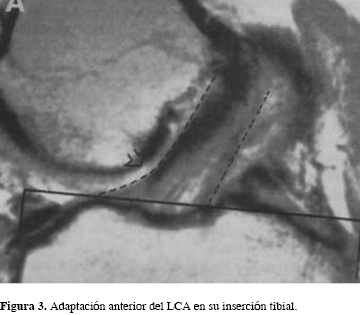

El LCA normal presenta una inserción tibial muy ensanchada, cerca del doble que en su origen femoral. Se ha considerado que la pendiente medial de la espina intercondílea medial representa el origen del margen medial del LCA nativo (Figuras 1 y 3).5 Estos hechos anatómicos hacen posible explicar que un injerto tubular o rectangular no puede reproducir el aplanamiento anterior de la inserción del LCA nativo.5